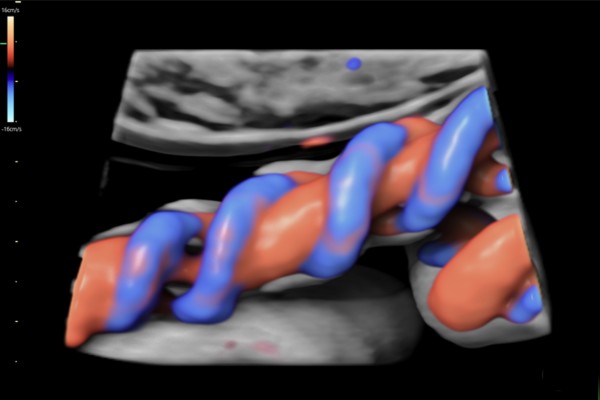

Doppler Placentario

Examina el flujo sanguíneo en la placenta y cordón umbilical, fundamental para detectar insuficiencia placentaria y garantizar la correcta nutrición del bebé.